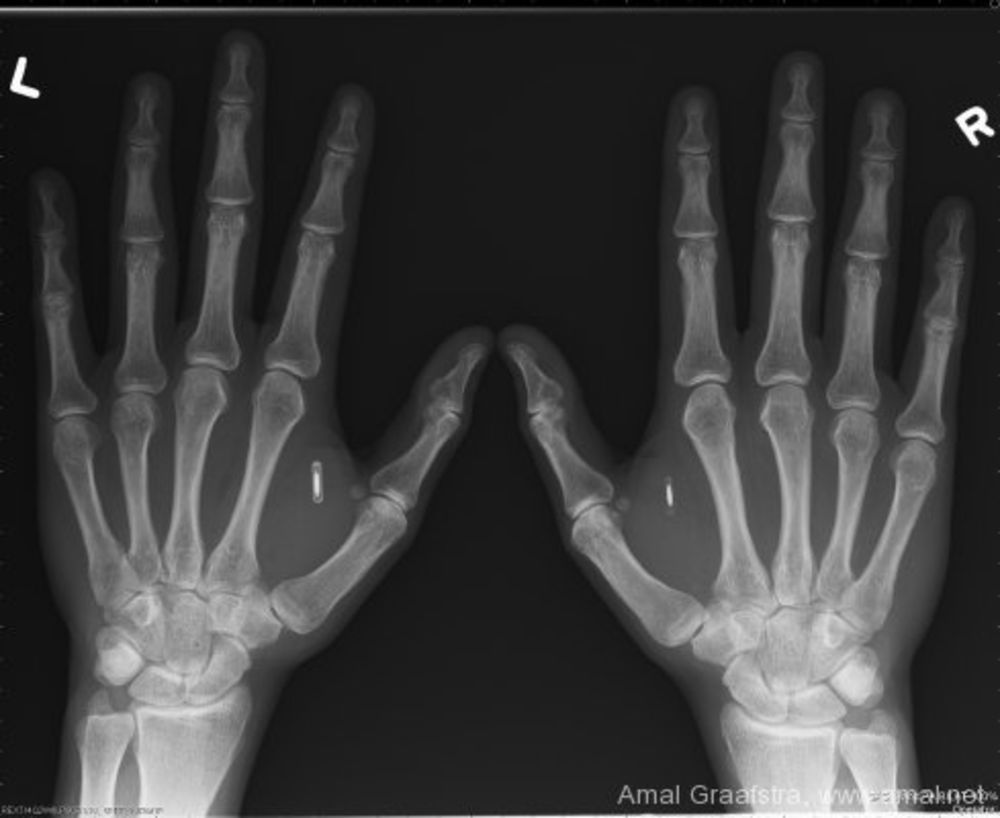

Et alors que Bill Gates vante les mérites et fait la promotion marketing du "vaccin" vital , qui est l'implantation d'une puce RFID (voir mes tweets pour tout savoir) pour marquer et contrôler les Humains sur toute la Terre (suite)